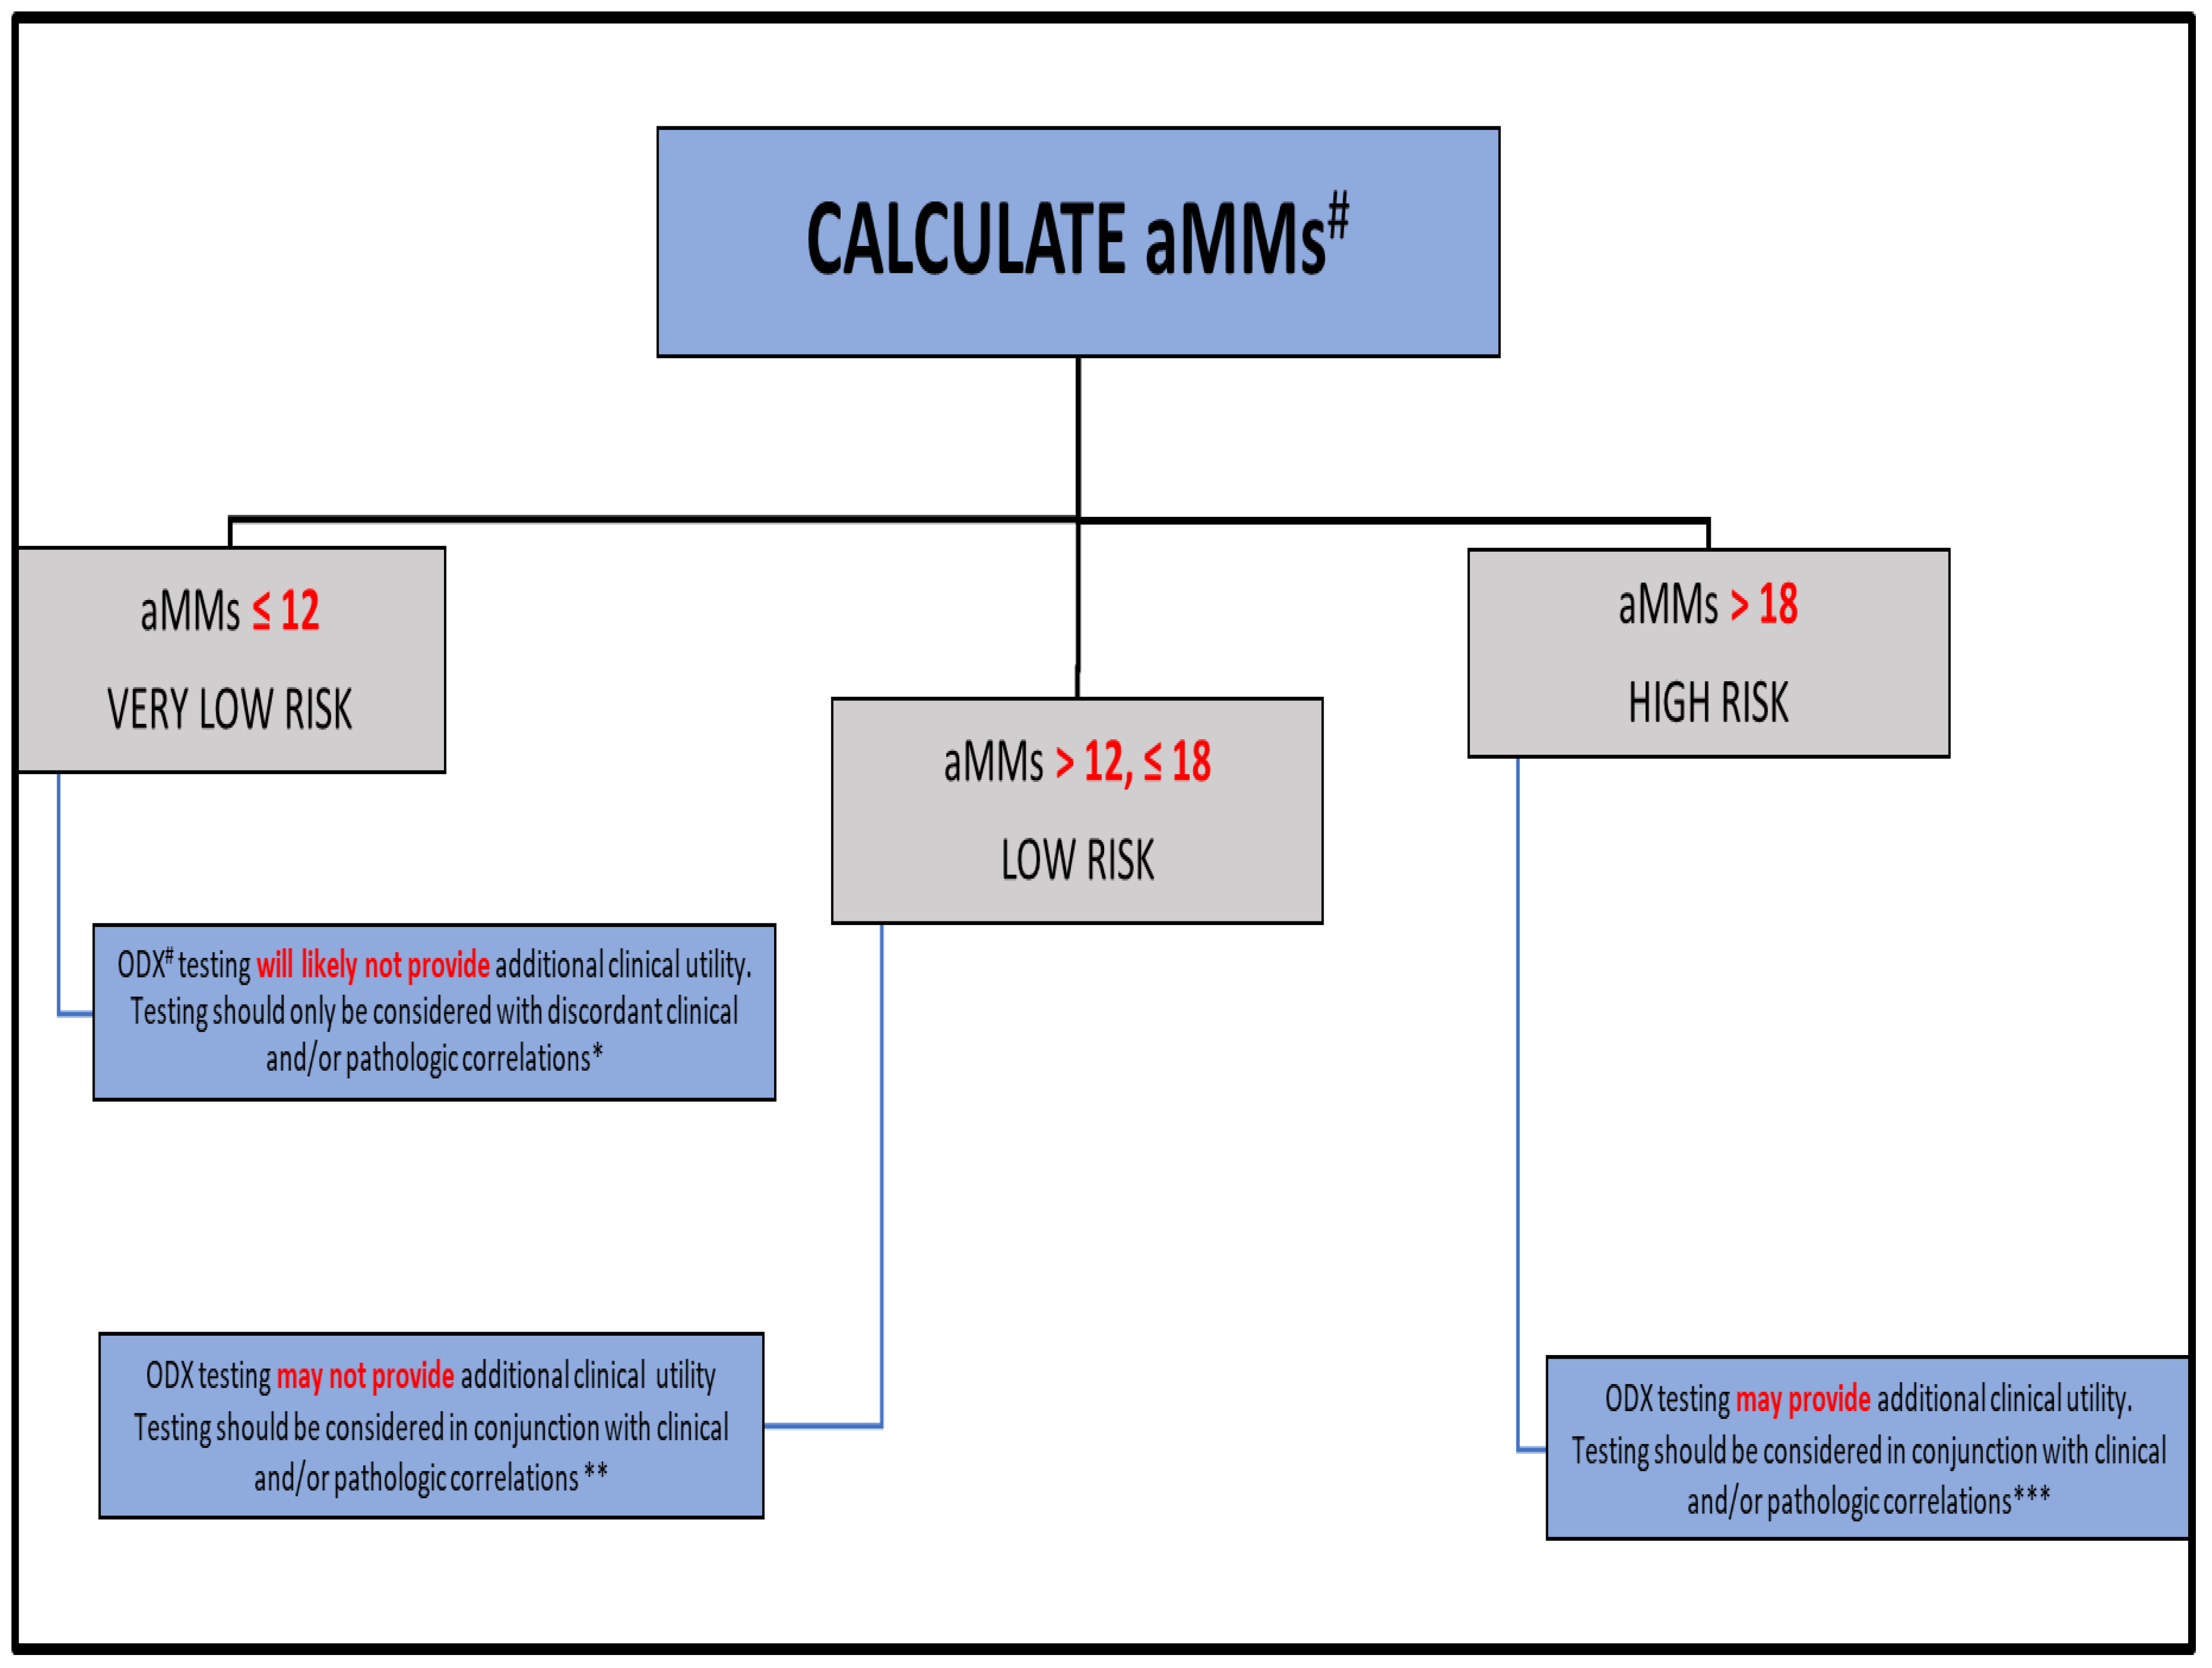

- Turner, B.M.; Skinner, K.A.; Tang, P.; Jackson, M.C.; Soukiazian, N.; Shayne, M.; Huston, A.; Ling, M.; Hicks, D.G. Use of modified Magee equations and histologic criteria to predict the Oncotype DX recurrence score. Mod. Pathol. 2015, 28, 921–931. [Google Scholar] [CrossRef] [Green Version]

- Bhargava, R.; Clark, B.Z.; Carter, G.J.; Brufsky, A.M.; Dabbs, D.J. The healthcare value of the Magee Decision Algorithm™: Use of Magee Equations™ and mitosis score to safely forgo molecular testing in breast cancer. Mod. Pathol. 2020, 33, 1563–1570. [Google Scholar] [CrossRef] [Green Version]

- Bhargava, R.; Clark, B.Z.; Dabbs, D.J. Breast Cancers with Magee Equation Score of Less Than 18, or 18-25 and Mitosis Score of 1, Do Not Require Oncotype DX Testing: A Value Study. Am. J. Clin. Pathol. 2019, 151, 316–323. [Google Scholar] [CrossRef] [PubMed] [Green Version]